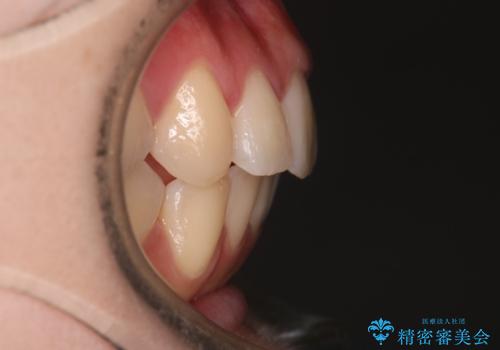

【インビザライン】マウスピースで開咬改善

- 開咬を主訴に来院されました。

IPR(歯と歯の間を削る処置)と顎間ゴムを行いながら、インビザラインで開咬を治療する計画を立てました。

治療をしながら、MFT(口腔筋機能療法)も行っていくことにしました。

歯の移動量が多いケースでしたが、患者様にマウスピースの使用とゴム掛けを頑張っていただいたので

リファイメント1回のみで治療を終わることができました。